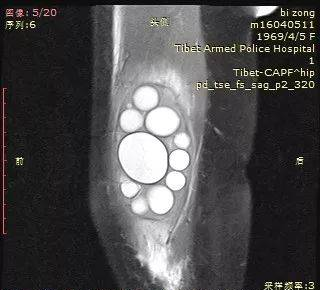

大腿包虫

典型

还是大囊包小囊

MRI显示更清楚